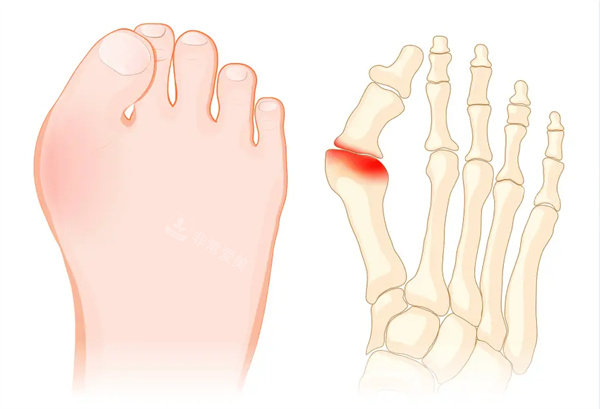

我的大脚骨问题由来已久。记得从青春期开始,我就发现自己的大脚趾逐渐向外倾斜,脚内侧也慢慢长出了一个明显的凸起。一开始,我并没有太在意,觉得这可能只是小问题。然而,随着年龄的增长,大脚骨的情况越来越严峻。

每次买鞋都成了一件痛苦的事情。漂亮的高跟鞋根本无法穿,因为只要稍微挤压一下,大脚骨的部位就会疼痛难忍。即使是平底鞋,也很难找到合适的款式,很多鞋子都会磨到脚骨,走路时那种钻心的疼痛让我苦不堪言。而且,因为大脚骨,我的脚型变得非常难看,夏天都不敢穿凉鞋,只能把脚藏起来。这不仅给我的生活带来了极大的不便,也让我变得越来越自卑。